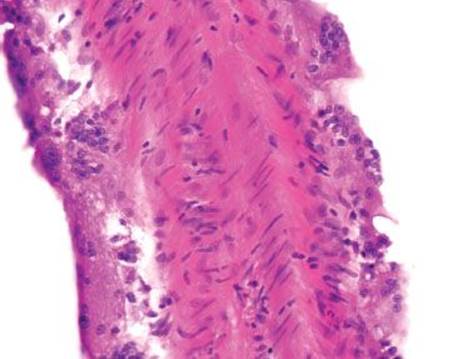

Figure 4.231 Melanosis coli, endoscopic image. This endoscopic image shows striking mucosal pigment deposition. This patient had a 10-year history of senna intake for chronic constipation.

Figure 4.232 Melanosis coli. The characteristic brown-black pigment is within the cytoplasm of macrophages. The pigment is lipofuscin, not melanin.